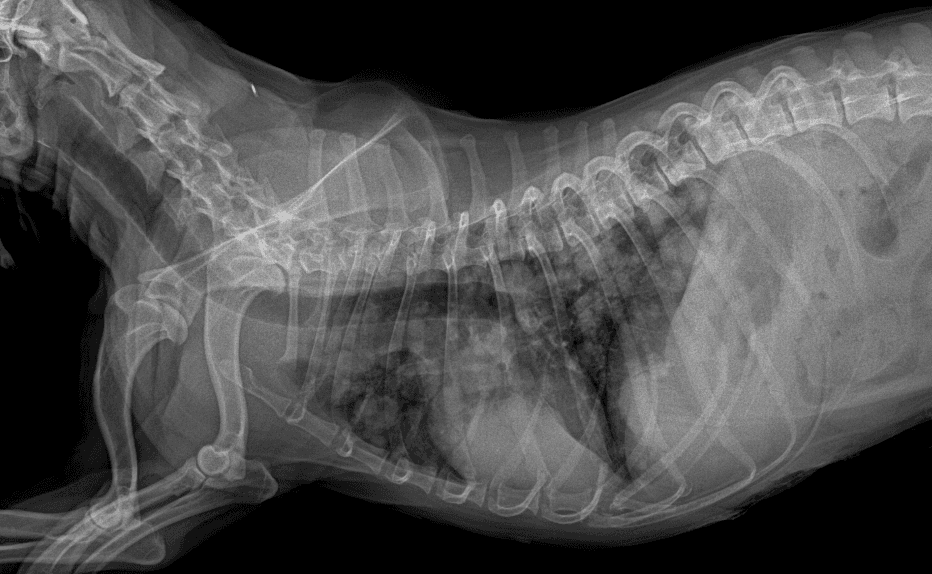

동탄 1 신도시 최초 Aquilion CX/128 slice CT를 동물병원에 도입하였습니다. 최고 사양 CT 모델 Aquilion CX/128 slice를 활용하여 0.5 mm의 얇은 128개의 단면 영상을 신속히 획득 할 수 있어 마취 시간을 단축시킬 수 있습니다. 또한, 128 슬라이스의 고화질의 CT 영상을 통해 영상 왜곡을 최소화하고 X-ray에서는 확인하기 힘든 5 mm 이하의 미세 병변도 확인이 가능하여 정확한 진단을 할 수 있습니다. 심화 진단이 필요한 경우, 조영제 인젝터를 통한 동맥기 촬영으로 종양 유래 확인, 간 질환 진단, 심혈관계 진단이 용이합니다. 저희 동탄시티동물의료센터에서는 본원 환자뿐 아니라 1차 동물 병원과의 CT 촬영 의뢰 시스템을 통해서 원활한 협진이 가능하도록 최선을 다하고 있습니다.

64채널 검출기 시스템 128

슬라이스 이미징 능력

고속 스캔 및 높은 해상도 제공

저선량 기술 적용으로 환자 방사선 노출 감소

0164 채널 CT 촬영을 통해서 신속하게 고화질 영상을 얻어, 종양 유래 확인 및 전이 평가, 간문맥단락증(PSS), 선천적 뼈 기형과 같은 심화된 진단을 할 수 있습니다.